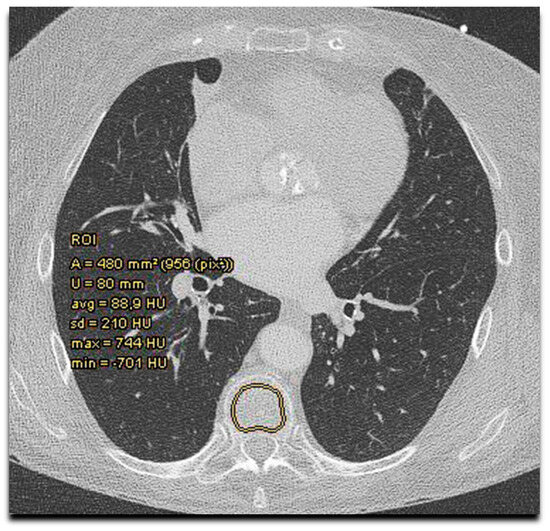

The obligatory TAVR-CT angiography scans were performed according to standard protocols [34]. In addition, a non-contrast-enhanced acquisition (120 KV, 3 mm slices) covering the area from the aortic root to the apex included coronary and aortic valve calcium scoring (CAC, AVC). For bone density measurement, HU values of thoracal vertebrae on the non-contrast CT scan were assessed (Figure 1). This was performed by Deep Unity, a widely used picture archiving and communication system (Dedalus HealthCare, Konrad-Zuse-Platz 1–3, Bonn, Germany).

Figure 1.

Bone mineral density assessment by Hounsfield units measurement on TAVR-CT scan. Bone mineral density (Hounsfield units) measurement in sternum and thoracal vertebra with determination of area (A), circumference (U), average (avg) density, standard deviation (SD), and maximal (max) and minimal (min) density in the region of interest (ROI).